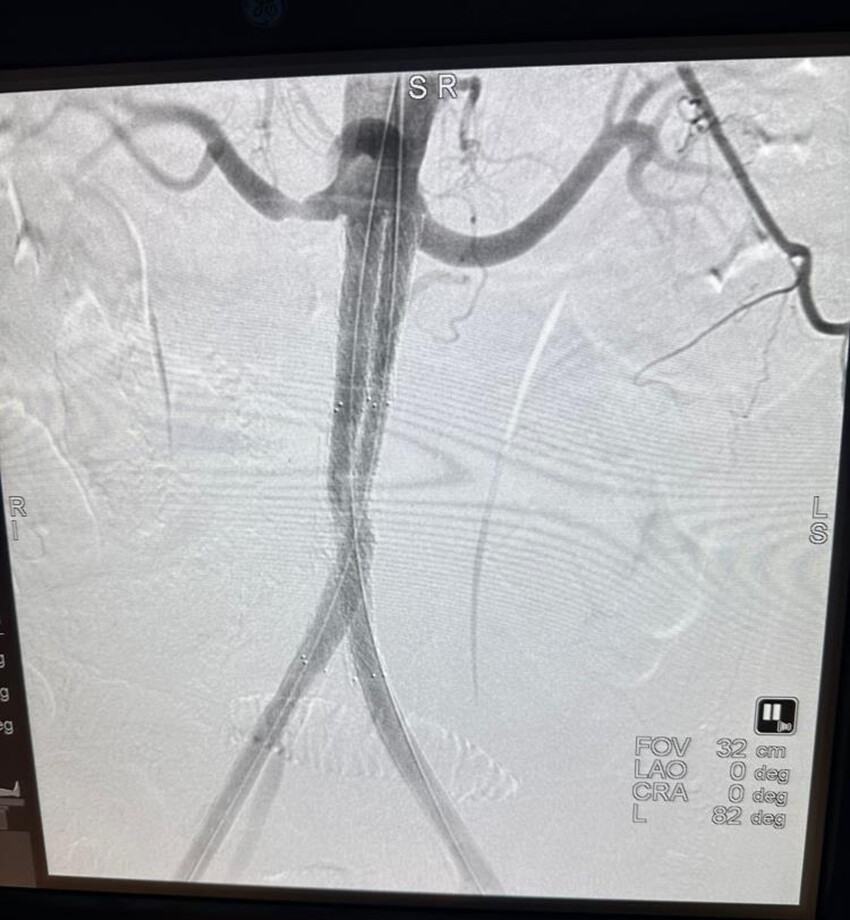

Hasta, ağrı, şişlik ve yürüme zorluğu gibi şikayetlerle hastaneye başvurdu. Yapılan tomografik damar film görüntülemesi sonucunda, hastanın iki bacağının kasık bölgesinden böbrek atar damar (renal arter) seviyesinin hemen altına kadar tıkalı olduğu tespit edildi. Uzm. Dr. Metin Onur Beyaz tarafından Leriche Sendromu teşhisi konularak hastanın tedavi altına alınması kararı verildi. Tedavi sürecinde Atlas Stent Greft ise teknolojisi kullanıldı. “Yapay damar" olarak bilinen Atlas Stent Greft, tıkalı damarların yeniden canlandırılmasını sağlamak için damar içine yerleştirildi. Sonrasında Stena Çok Katmanlı Periferik Akım Çevirici Stent uygulaması yapılarak işlem başarılı bir şekilde tamamlandı.

Stent greft veya diğer adıyla "yapay damar", damarın içine yerleştirilerek tıkalı bölgenin genişletilmesi ve normal kan akışının yeniden sağlanması amacıyla kullanılıyor. INVAMED tarafından üretilen Atlas marka Stent Greft, damar içinde oluşan balonlaşmaları veya yaralanmaları tedavi etmek için özel olarak tasarlanmış bir tıbbi cihaz olarak ön plana çıkıyor. Bu cihaz, damarı destekleyerek doğru kan akışının yeniden sağlanmasına yardımcı oluyor.